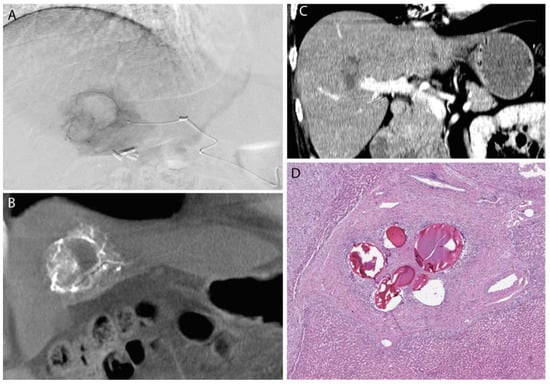

Gelatin sponge is a non-antigenic carbohydrate prepared from purified skin gelatin. Gelatin sponge has a highly porous microscopic structure, allowing for absorption of up to 45 times its weight in fluid [9]. Like PVA, gelatin sponge has been used in medicine for over half a century, as it was initially introduced as a pro-coagulant for surgical patients in the 1940s. Also like PVA, gelatin sponge has been used as a transcatheter embolic agent for a broad range of clinical applications, including embolization of renal tumors and for emergent pelvic bleeding [6] (Figure 1). Gelatin sponge is commercially available as a powder or a sheet that can be cut to size; the powder form contains particles that are generally considered too small for clinical use, given the risk of ischemia by very distal embolization.

Figure 1.

A large benign solitary fibrous tumor of the right pleura (A) was pre-operatively embolized with Gelfoam; (B) surgical resection photograph; (C) angiography of the right phrenic artery demonstrated exuberant vascularity within the mass; (D) histology demonstrates fragments of Gelfoam (acellular pink material) within blood vessels in the mass which is entirely infarcted.